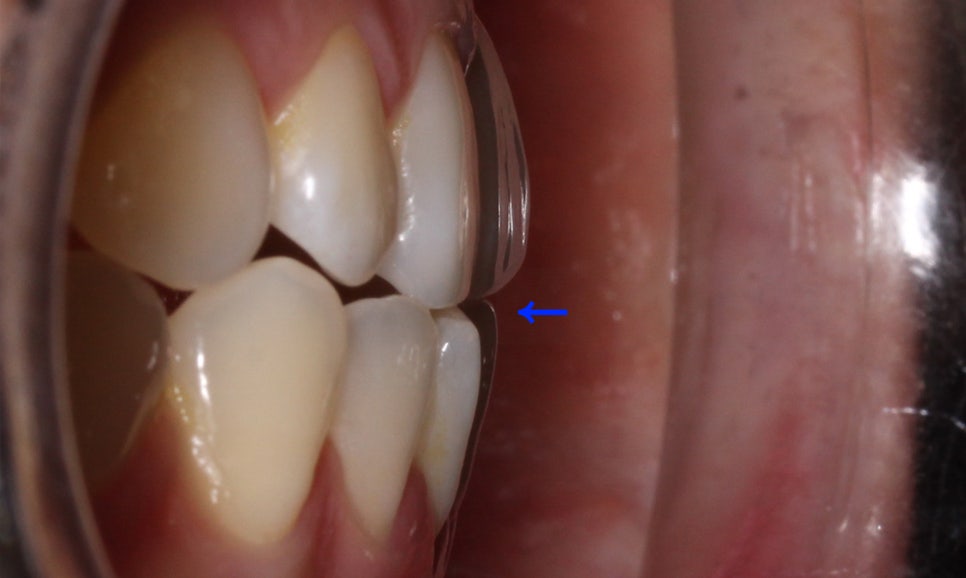

클리피씨 교정 후 전치부의 overbite 수치를 보면

교정 전과 달리 상하악이 바르게 교합되는

모습을 확인할 수 있는데요,

교정 전 부정교합으로 인해 전치부의

수직피개가 0에 가까웠다면

교정 후 약 2mm정도로 개선된 모습입니다.

교정 후 전치부의 절단교합 증상이

많이 완화된 모습으로 overjet 사진에서

바른 교합 상태를 확인할 수 있는데요,